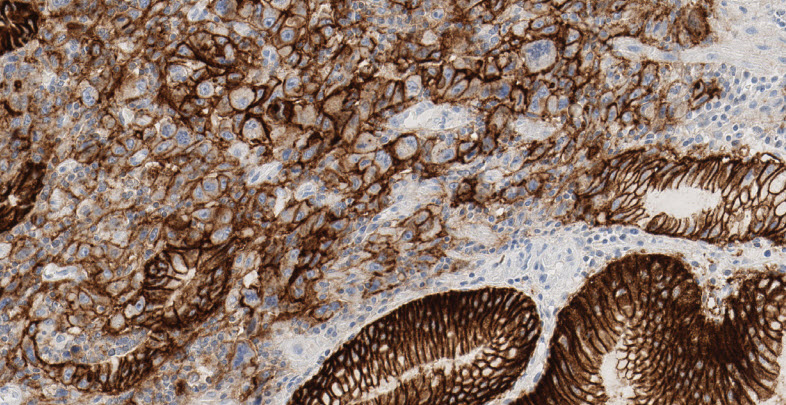

ベンタナ OptiView CLDN18(43-14A) トレーニングプログラムベンタナ OptiView CLDN18(43-14A) を用いた胃がんにおける免疫染色の判定について学んでいただけます